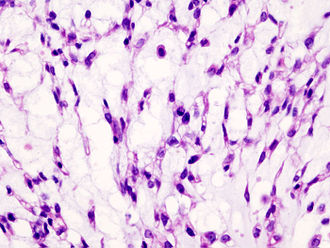

Chondrosarcoma. H&E stain. | |

| LM | "abnormal cartilage": +/-high grade changes - nuclear atypia (nuclear clearing, nucleoli, hyperchromasia), low/intermediate grade changes - bi-nucleation, hypochromatic enlarged nuclei, infiltration of lamellar bone ("invasion"), increased cellularity, irregular spacing of chondrocytes |

Microscopic

- "Abnormal cartilage":

- +/-Nuclear atypia - high grade lesions.

- High grade lesions:

- Nuclear clearing.

- Nucleoli.

- Hyperchromasia.

- Low/intermediate grade lesions:

- Bi-nucleation.

- Hypochromatic enlarged nuclei.

- Infiltration of lamellar bone ("invasion") - not common - diagnostic.

- Increased cellularity.

- More cellular than cartilage... but relatively paucicellular compared to other sarcomas.

- Irregular spacing of chondrocytes.